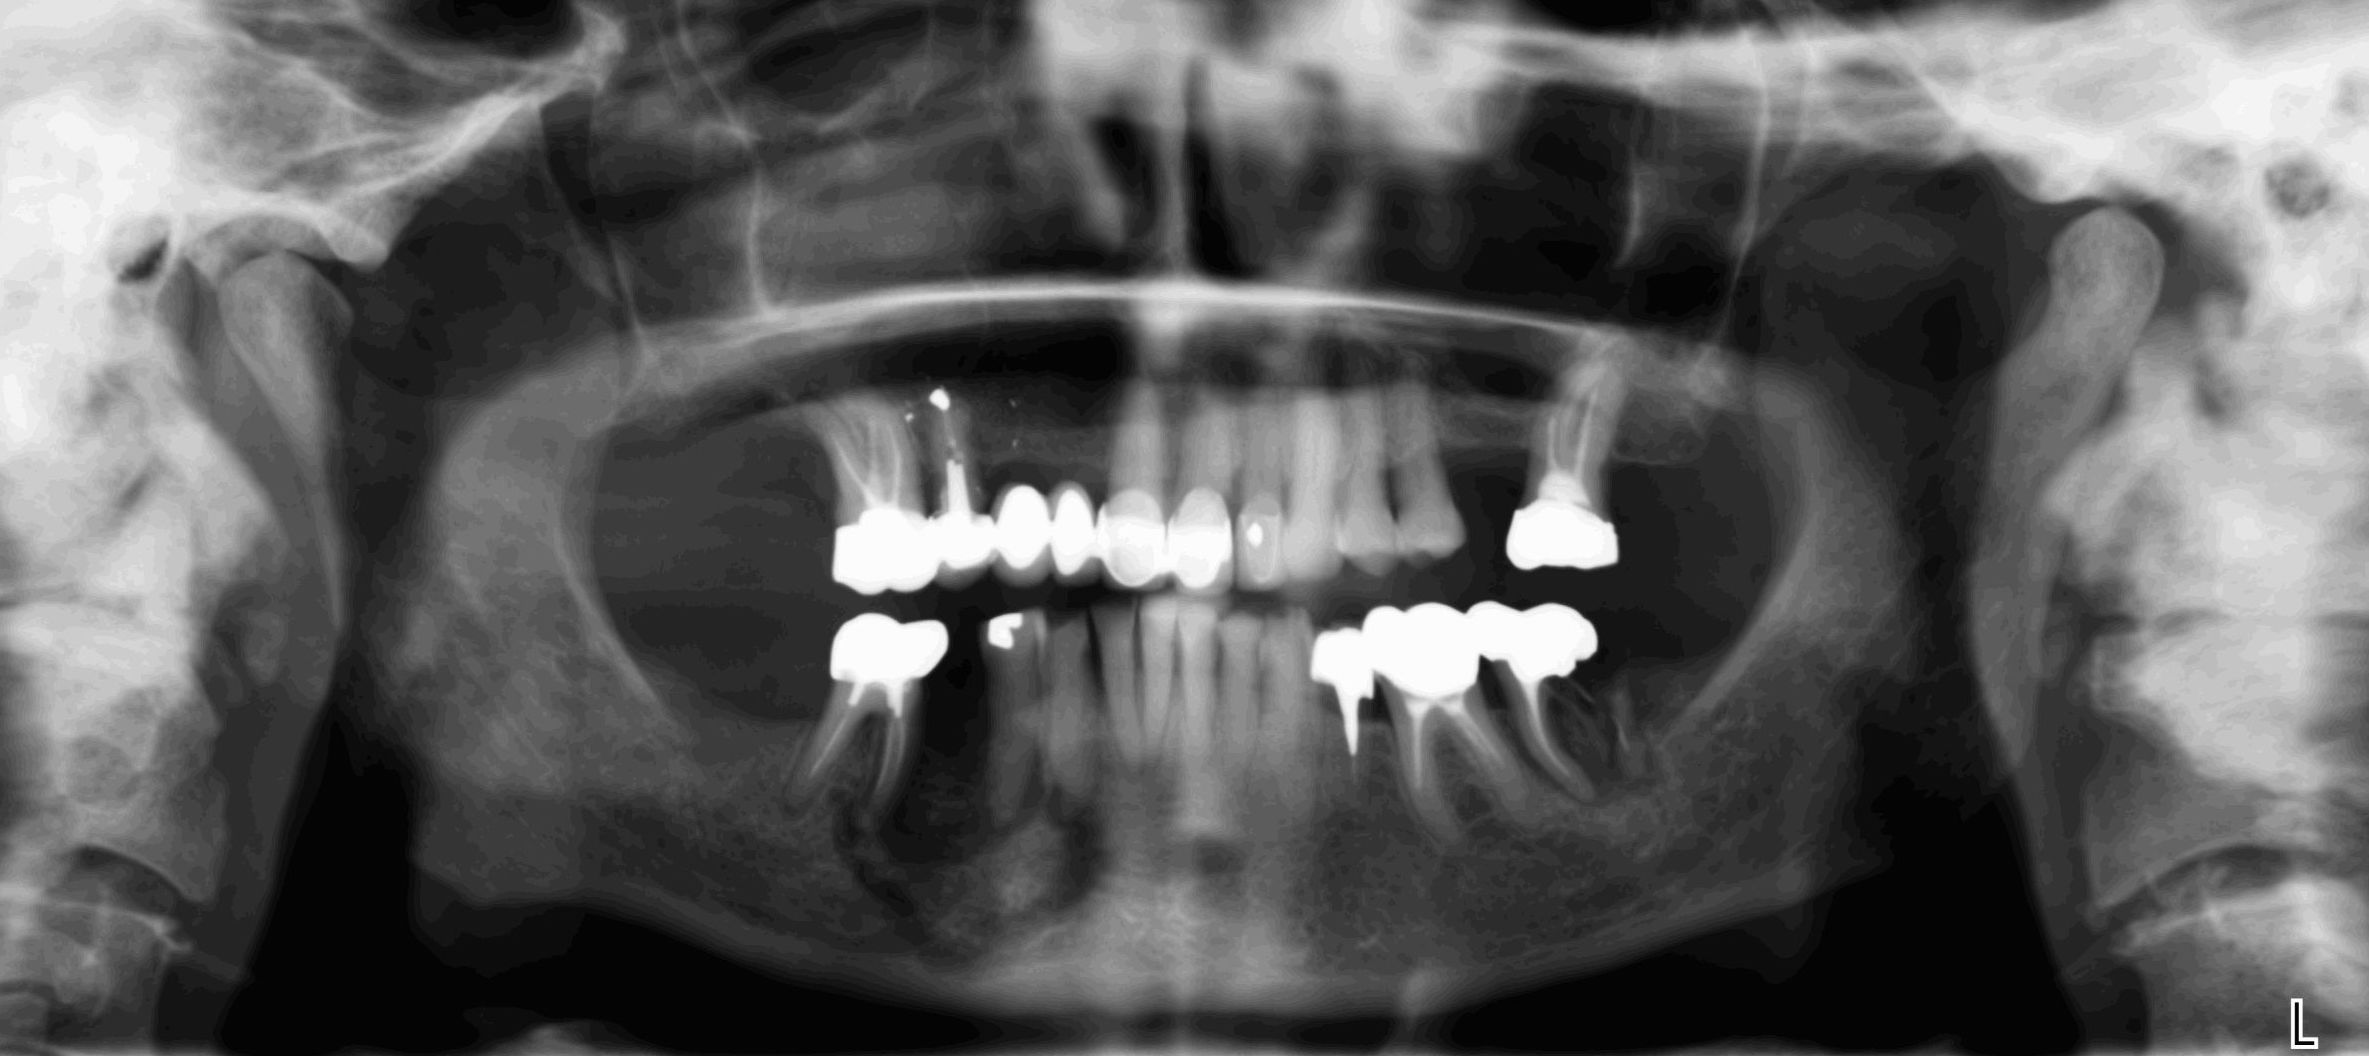

Ce sont les examens de référence en imagerie dentaire avec les clichés rétroalvéolaires que votre dentiste fait directement dans son cabinet.

-pour le panoramique dentaire l'appareil tourne autour de vous, votre tête est installée dans l’appareil et maintenue par un système de contention. Une pièce en plastique sera placée entre vos dents de manière à ce que vous mâchoires soient légèrement écartées. L’acquisition du cliché dure environ 10 à 20 secondes durant lesquelles vous devez rester immobile.

Images de panoramiques dentaire:

Les nouvelles générations de scanner permettent de faire une acquisition d’un volume global d’une partie du corps et de travailler à l’intérieur de ce volume en isolant une structure anatomique donnée et de l’explorer dans tous les plans de l’espace.